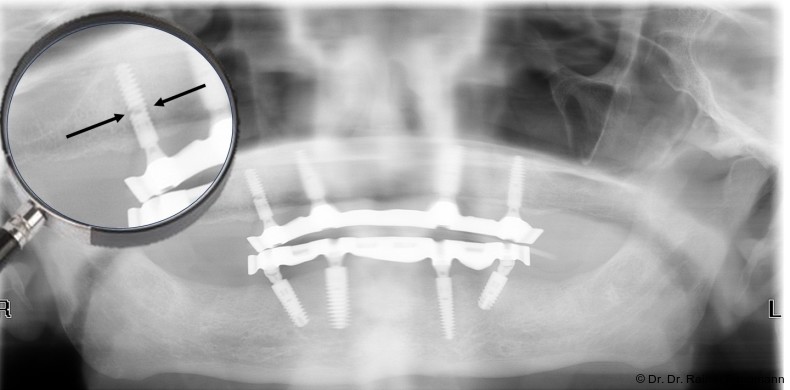

Sheffield-Test

Der Sheffield-Test ist eine aussagefähige Überprüfungsmethode des passiven Sitzes von zahnärztlichen Mesostrukturen.11 Dabei zeigt er eindeutig die Passung oder Fehlpassung der Mesostruktur auf dem Modell und im Mund an. Mit einer Schraube wird die Mesostruktur auf dem Modell am distal positionierten Modellimplantat oder Abutment zur Kontrolle festgeschraubt.12 Dabei darf kein Spalt zwischen Mesostruktur und den restlichen Abutments bzw. Implantaten vorhanden sein. Wird eine Spaltbildung festgestellt, liegt eine Passungenauigkeit vor. Diese Passungskontrolle wird wechselseitig an der Mesostruktur vorgenommen. Dieser Test wird bei der Steg- oder Brückeneinprobe im Mund des Patienten wiederholt. Eine röntgenologische Überprüfung bei verschraubten Mesostrukturen reicht als Qualitätsmerkmal für einen passiven Sitz nicht aus, gibt aber einen ersten Hinweis.

Im dritten Beispiel erfolgte die Abformung nicht auf Abutmentniveau, sondern auf Implantatniveau. In diesem Beispiel wurden die Abutments mit dem CAD/CAM-Steglaborseits verklebt. Um die Eingliederung in der Mundhöhle zu ermöglichen, wurden die Abutments am Verbindungselement zum Implantat beschliffen. Das wirdseitens des Implantatherstellers nicht empfohlen. In einem vierten Beispiel kam es acht Wochen nach der prothetischen Versorgung zum Implantatbruch. Das Implantat zeigt an der Fraktur einen deutlichen Versatz. Der Steg zeigte auf den restlichen Implantaten eine spürbare und sichtbare Spannung. Hier liegt der Fehler sicherlich in der Abformung. Zumindest wurde die Spannung bei Insertion des Stegs auf die Implantatabutments vom Prothetiker nicht registriert. In einem fünften Beispiel kam es nach vier Jahren zur Implantat- und Abutmentfraktur. Hier ist das Geschehen auf den gleichen Mechanismus wie im Beispiel Vier zurückzuführen. Es zeigt sich eindeutig ein Anwenderfehler. Im Nachgang kann davon ausgegangen werden, dass der Steg von links nach rechts verschraubt und so die Spannung aufgebaut wurde, die für das Frakturgeschehen ursächlich ist.